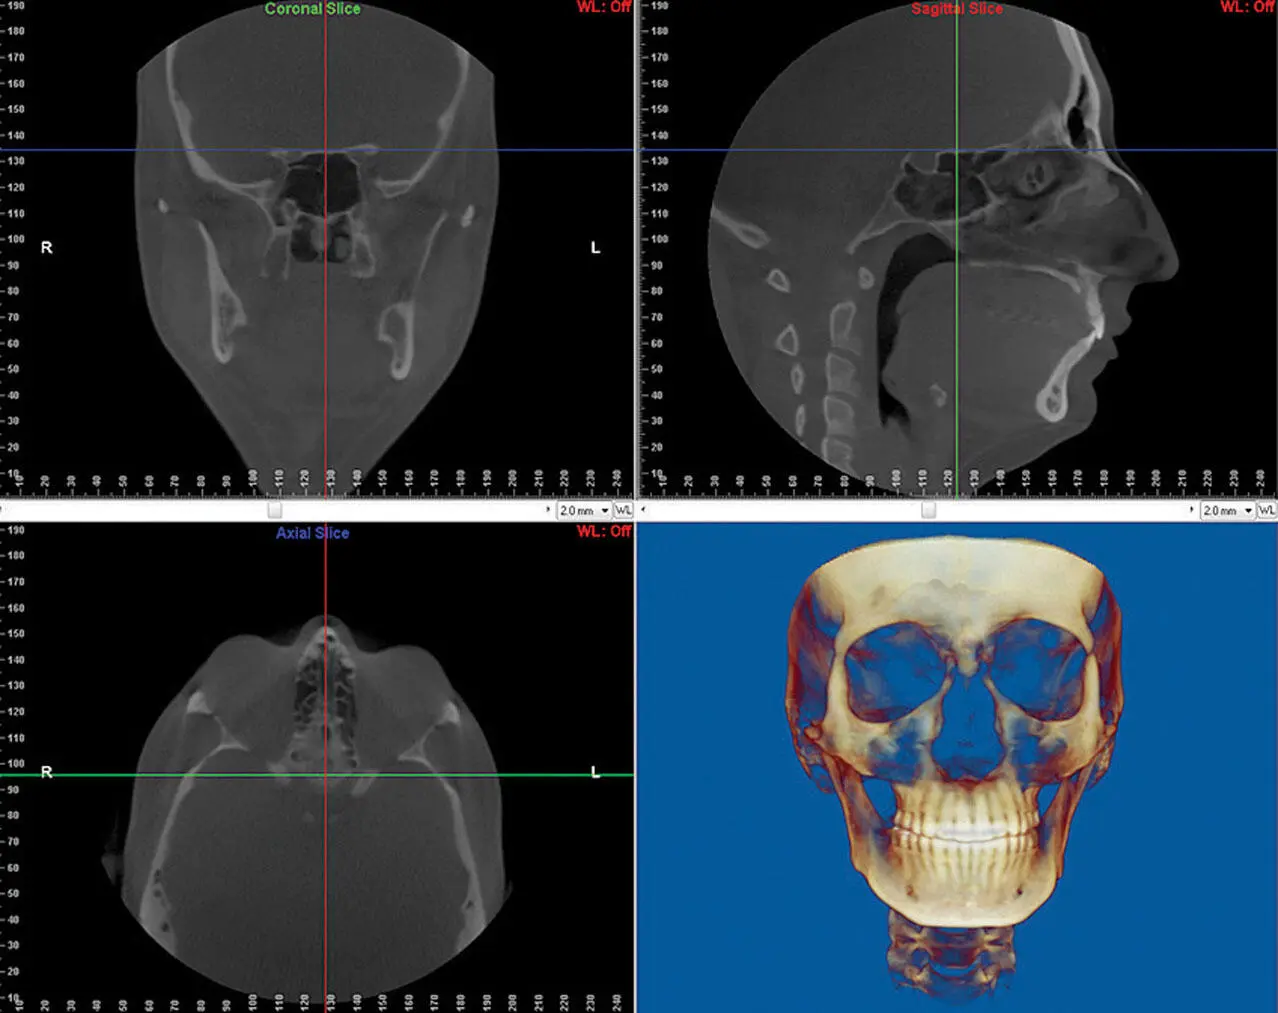

Fig 1-2Software screen showing (a) coronal slice ( green line in b and c ), (b) sagittal slice ( red line in a and c ), (c) axial slice ( blue line in a and b ), and (d) 3D CBCT reconstruction of the same study.